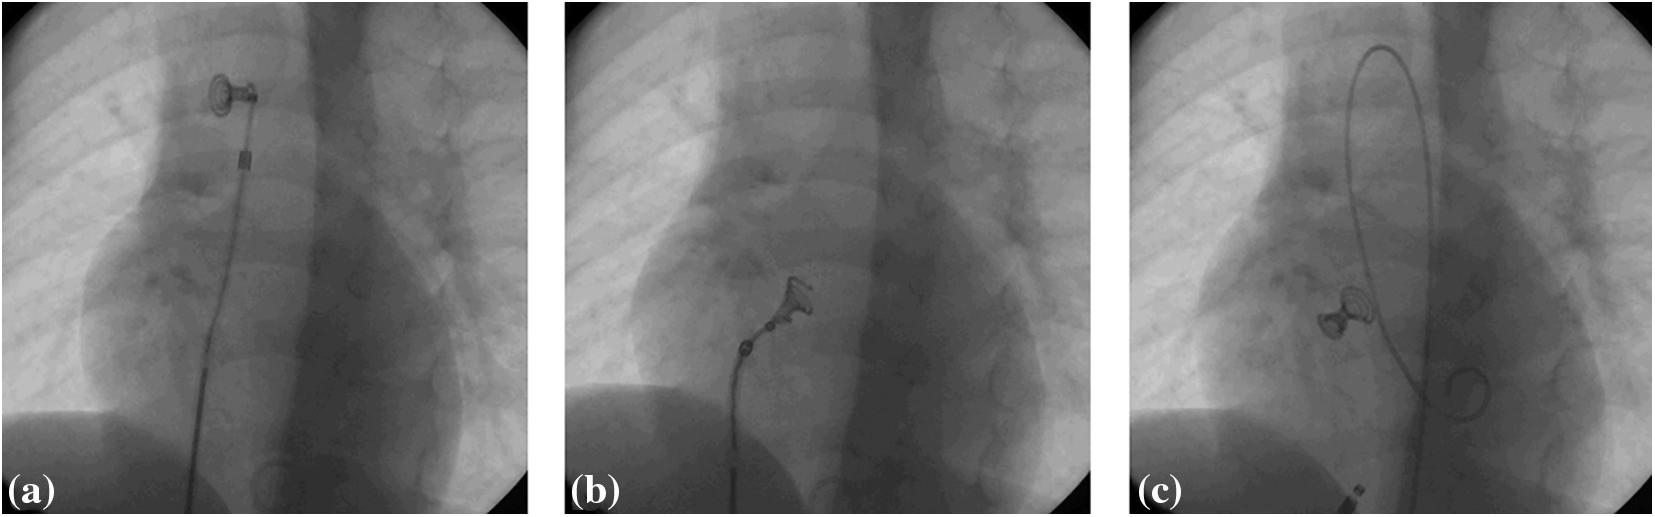

All the patients were subjected to pre-interventional transthoracic echocardiography and routine laboratory analyses. Catheterisations were performed under general anesthesia, with pre- and post-procedural antibiotic prophylaxis and heparinisation during the procedure (heparin bolus of 100 IU/kg body weight). Almost all of the interventions (27/30) were carried out in cooperation with the international proctor who participated in designing the device (Dr. Trong Phi Le, Heart Center Bremen, Klinikum Links der Weser, Germany). Initially, left ventricular angiogram was made in order to define the size and location of the defect. The VSD diameter was measured at the diastolic phase and an occluder was selected based on the largest measurement. The device implantation technique (Fig. 1) was described in detail in previous publications [4,6].

Figure 1: The final steps of Nit-Occlud Lê VSD coil implantation. (a) Complete left coil is deployed in ascending aorta; (b) the whole system is retracted through the aortic valve and left ventricle until the coil enters VSD and the final two loops are deployed at the right side of the defect; (c) if the position of the device is considered adequate, it is released